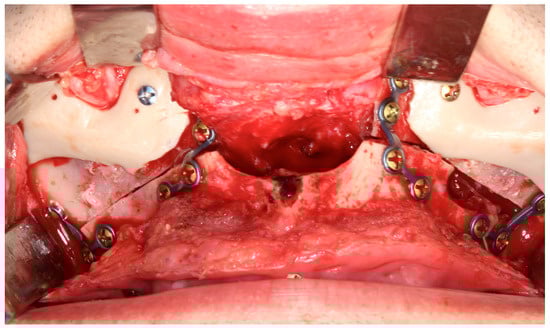

Mandibular angle augmentation during orthognathic surgery is technically demanding (Figure 6) due to the complex anatomy of the pterygomasseteric sling and its functional relationship with the masseter muscle [30]. Careful subperiosteal dissection along the inferior mandibular border is required to preserve the muscular sling, as disruption may cause superior masseter retraction and hollowing of the angle [10,30,33]. Intraoperative strategies to minimize complications include epinephrine infiltration, wide intraoral incisions for visualization, strict subperiosteal dissection, and stable screw fixation. Augmentation should respect the patient’s soft-tissue envelope and masseter strength, particularly in hypodivergent or brachyfacial patients, to avoid over-contouring or implant stress, thereby reducing the risk of malposition, asymmetry, and revision [10,33].

Figure 6. Standard mandibular angle implants. When used in combination with a mandibular osteotomy, adaptation of the implant design is required. Although this remains a viable surgical alternative, it demands additional operative time and meticulous positioning to ensure adequate bone contact and stability. Using PSI, this adaptation can be planned in advance, positioned safely away from the osteotomy line and the fixation point—Image from the authors’ personal archive.